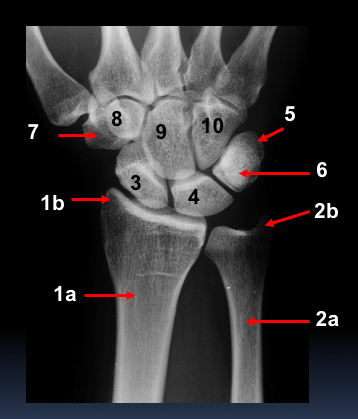

What are the labels?

1a - distal shaft of radius

1b - styloid process of radius

2a - ulna distal shaft

2b - styloid process of ulna

3 - scaphoid

4 - lunate

5 - triquetrium

6 - pisiform

7 - trapezium

8 - trapezoid

9 - capitate

10 - hamate

What is the radial styloid? What is the ulna styloid?

Styloid process is found at the distal end of both the ulna and the radius - is a projection of bone

Radial - projection on the lateral surface of the distal radius

Ulna - projection on the medial surface of distal ulna